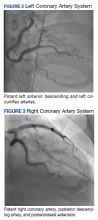

The patient was taken for emergent coronary catheterization, which demonstrated patent epicardial coronary arteries without atherosclerosis, a left ventricular ejection fraction of 60%, and a right dominant heart (Figures 2 and 3). Ventriculogram showed normal wall motion. Repeat troponin-I several hours after catheterization was again below detectable levels.

Left and Right Coronary Artery System figure